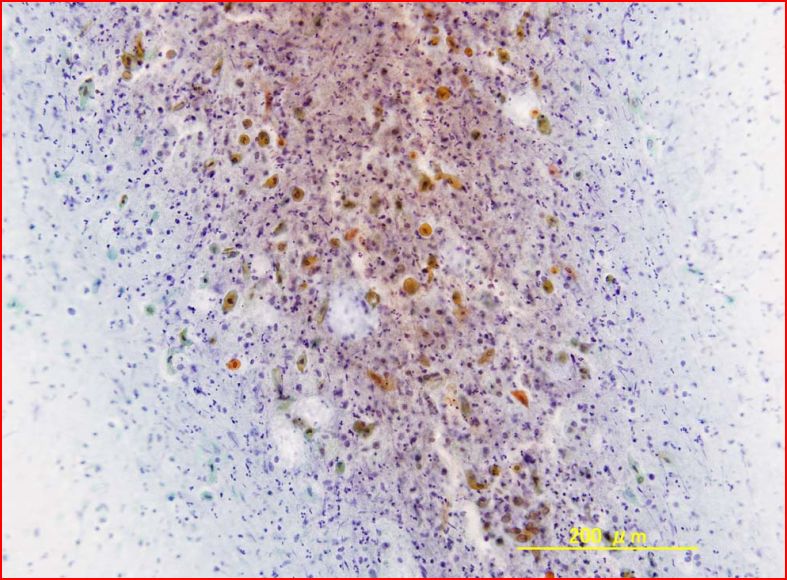

組織所見

組織では、広い好酸性の胞体を持つ細胞が、腺管状・嚢胞状構造を形成し、間質には胚中心の形成を伴うリンパ濾胞の発育を見るワルチン腫瘍の像であった。

嚢胞状構造の中には壊死物質の貯留が見られた。一部の上皮は基底部で円柱形細胞が縦に並び、上に行くに従って胞体が広くなり、最上部では細胞が横に扁平となる扁平上皮化生の像が見られた。

細胞診では、この最上部の細胞が角化細胞として観察されたものと考えられる。

ワルチン腫瘍では、時として扁平上皮化生による角化細胞が見られることがあり、扁平上皮癌と誤診しないように留意することが重要と思われる。